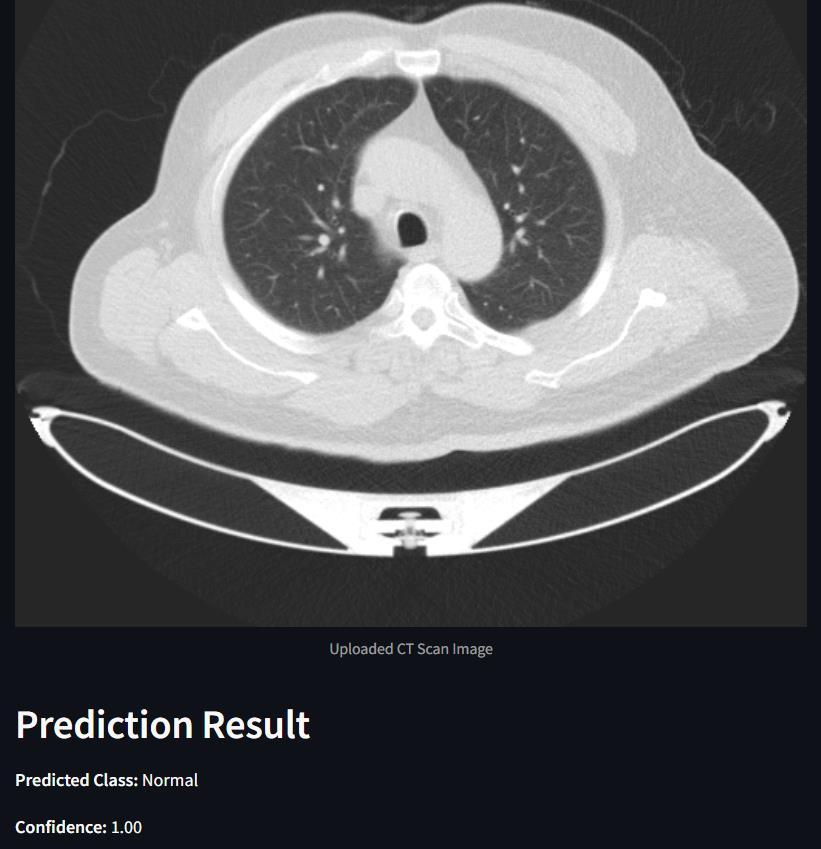

The final accuracy and performance metrics of the model are substantiated visually through a series of graphs and charts, showcasing accuracy and loss metrics across epochsforbothtrainingandtestingdatasets.Additionally, confusion matrices are created to represent classification performanceonbothtrainingandtestingdata,providinga clear and concise understanding of the model's behavior. Complementing these metrics are tumor images displaying predicted classes alongside model confidence scores, offering valuable insights into the model's effectiveness and emotional impact. This comprehensive presentationnotonlyevaluatesefficacybutalsofacilitates furtherrefinementandoptimization,ultimatelyenhancing overallperformanceforend-users.

The VGG- 16 model's performance on the IQ- OTH/ NCCD lung cancer dataset is exhaustively presented through a collection of visual aids. These include graphs and charts depicting accuracy and loss metrics over epochs for both trainingandtestingdatasets.Likewise,confusionmatrices are generated to illustrate the classification performance of the model on both training and testing data. This detailed representation offers precious perceptivity into the behavior and efficacy of the VGG- 16 model on the specifieddataset.

Output: